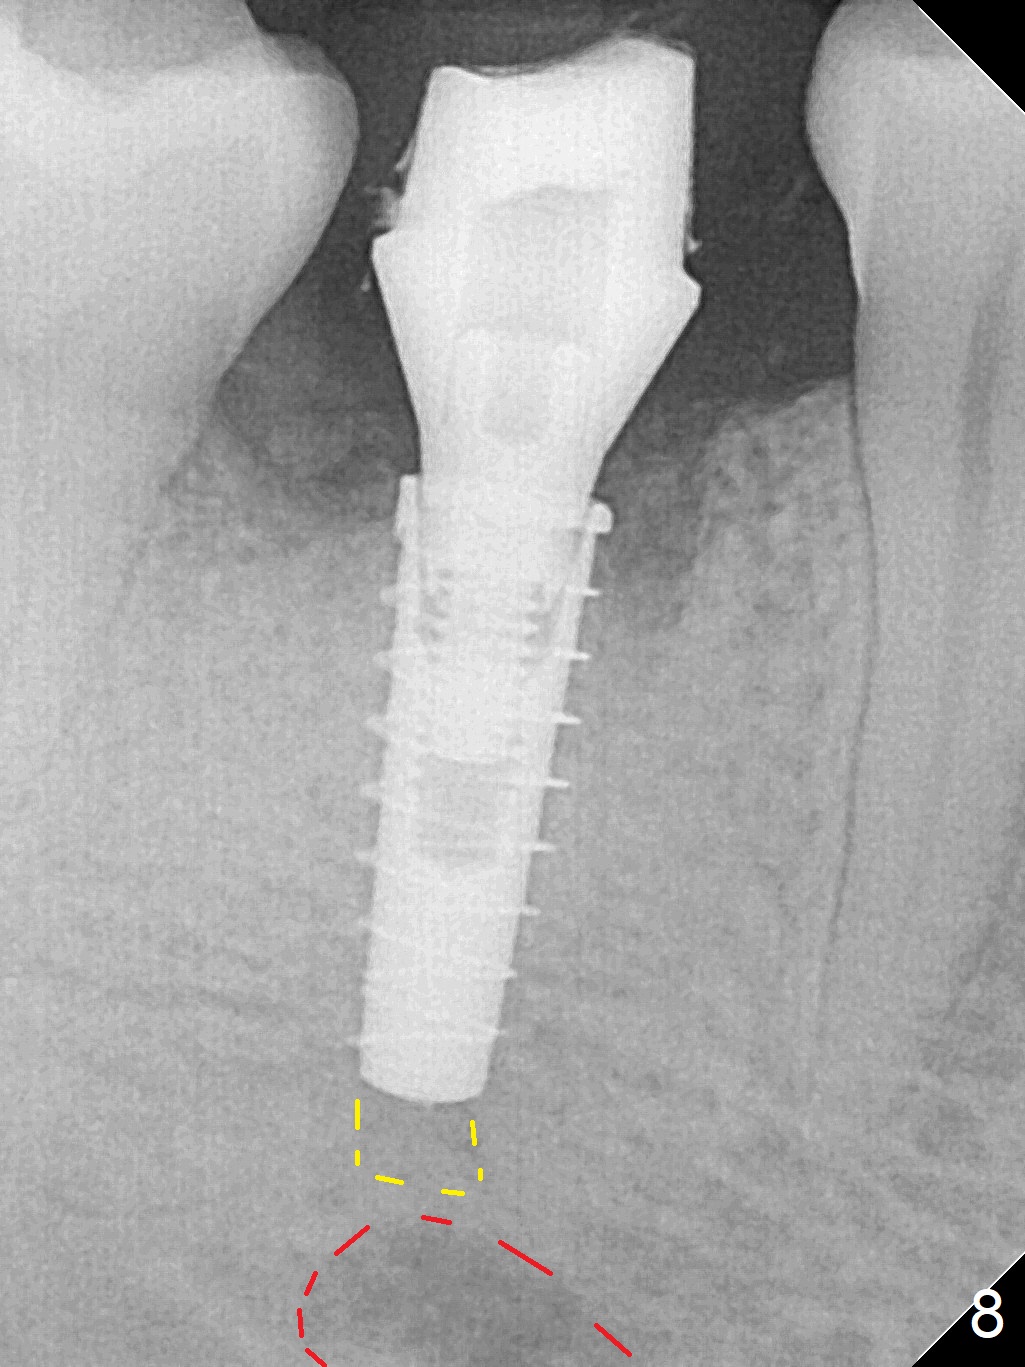

The lower 2nd primary molar has buccal furca lesion (Fig.1 *) with the thin buccal plate (Fig.2). Osteotomy is initiated in the sloped septum (Fig.3). After use of Magic Drill (MD) 3.3 mm for 13 mm and MD 3.8 mm for 11 mm, placement of a 4x11 mm IBS implant meets resistance because of the dense bone (Fig.4-6, red dashed line: Mental Loop) with final insertion torque >50 Ncm. After placement of a 6x4(3) mm abutment and autogenous bone in the remaining shallow sockets (Fig.6), a provisional is fabricated (Fig.7). Finally periodontal dressing is applied. Impression is taken 3 months postop (Fig.8). Buccal infection develops 2 weeks post cementation (Fig.9). When the crown/abutment is removed, there is no residual cement. The implant threads can be felt through the fistula. After soft tissue debridement and copious irrigation, Arestin is placed in the fistula. The latter disappears 15 days post debridement. The patient feels better and moves out of state. It appears that early periimplantitis develops because of the preexisting buccal furca lesion and failure to place the implant deep. The implant will be placed deep after loosening a little (since there is apical space (Fig.8 white line)) or removed, truncated at the apex and placed lower than the buccal crest.